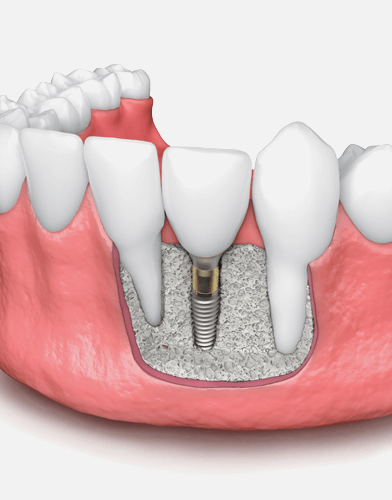

補骨手術是為了在植牙前幫牙齒打好地基,也就是「補骨粉」,其原理是利用人工骨粉或骨塊置入齒槽骨中,讓自體的骨質細胞沿著生長,使齒槽骨能生長完整。補骨手術填入骨粉後,能促使骨頭再生,待齒槽骨恢復穩固後,就能植入植體,讓植牙能更穩固,也能延長壽命。

簡單的補骨手術,會在骨缺損處填入骨粉、骨塊等材料,再覆蓋上再生膜,隔絕外界刺激,最後縫合,僅需局部麻醉,約30分鐘即可完成。

將人工骨粉或是骨塊,置入齒槽骨,補骨粉會建立一個架構,讓自體骨質細胞沿著生長。齒槽骨萎縮嚴重者,須等待骨頭新生完整,才能進行植牙;輕微者,植牙、補骨可同時進行。